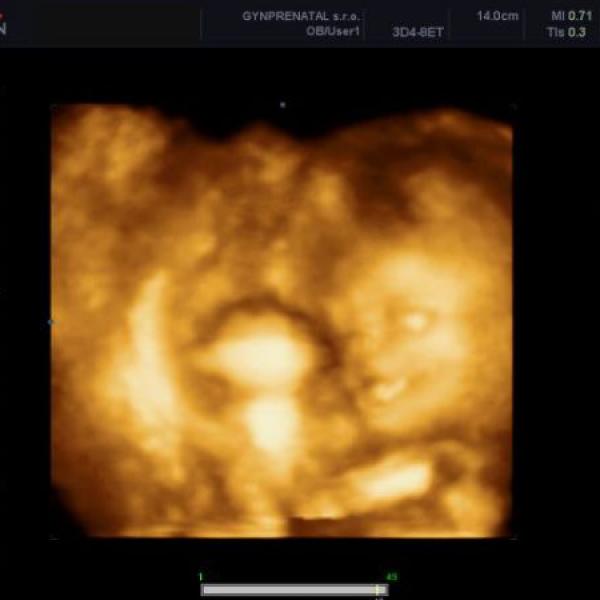

Ahojky holky, mám takový dotaz je tady taky nějaká maminka podobně v tomto týdnů,co už má mimi otočené hlavičkou dolů? Zdá se mi to docela brzo a na to,že už jsem i na palec oteřená, nevím co si mám myslet...zda se prcek ještě otočí nebo se mu chce už třeba ven...Barča...